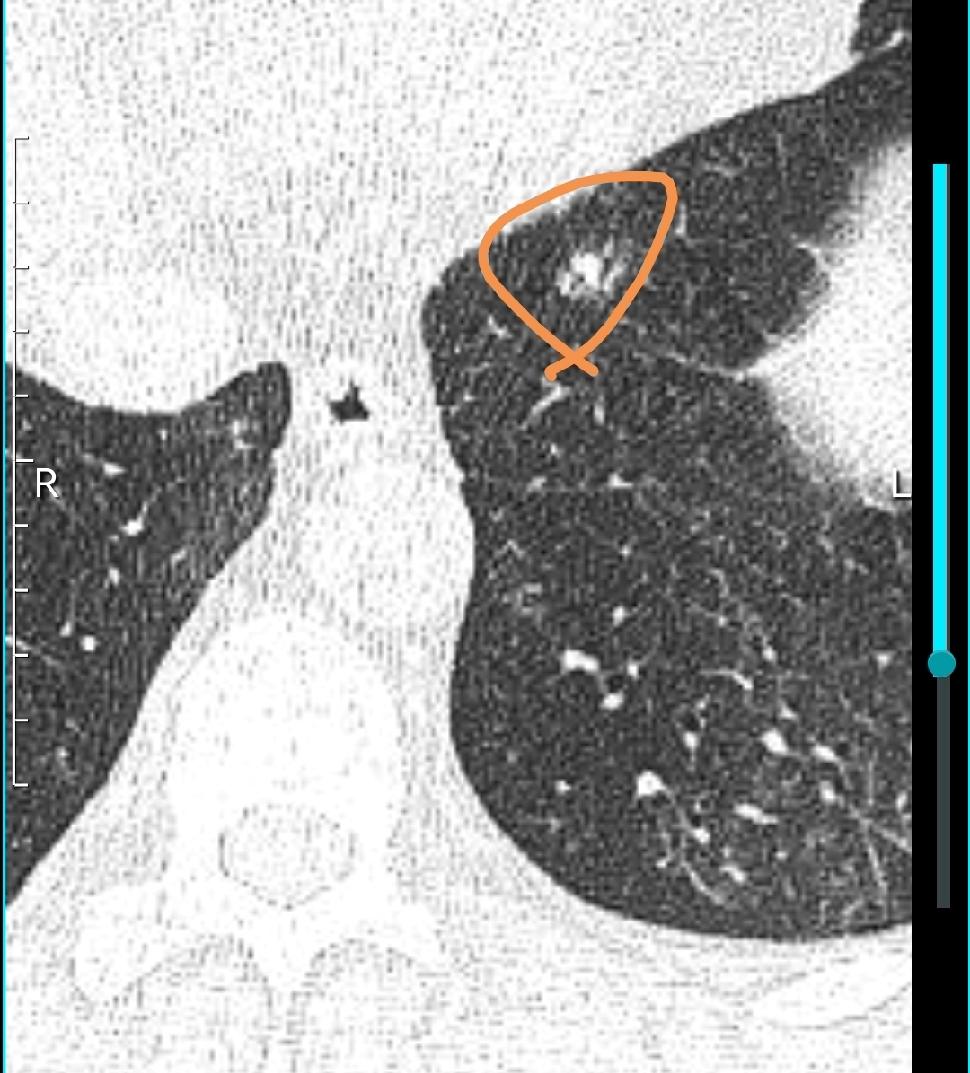

为什么有些肺部结节手术后会复发,现在很多科普视频,常常强调早期肺癌可以根治,但忽略了少部分肺部结节根治不了的事实,手术后1~2年内复发,复发后就没有办法完全根治,哪些因素影响术后根治率?

第一肺部结节当中癌细胞的亚型,如果含微乳头型、乳头型、复杂腺体、实体性等亚病理类型的癌细胞数量较多的话,术后复发的概率要成倍的增长,有些复发率甚至跟中期肺癌差不多。

第二,癌细胞侵犯的范围,侵犯的范围越小,复发率越低,比如说原位癌侵犯的范围最小,几乎不会侵犯到血管,这种情况根治率可以达到100%。如果病理当中出现侵犯的脉管神经胸膜等结构,则根治率明显下降。

三肿瘤的大小,理论上讲,肿瘤越大,根治率越低,大的肺部结节。通常也意味着恶性程度更高,侵犯的组织结构更多,有潜在的转移的风险,有些转移到淋巴结,但术前检查发现不了,术后就有复发的可能性。

所以发现结节是否手术,要根据多种因素来判断。肿瘤直径越大,密度越高,越靠近肺门越应该早一点考虑手术,降低术后复发率。结节结节 预防治疗肺结节